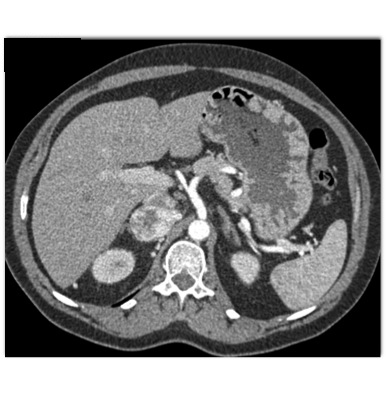

The best diagnosis in this case is

adrenal pheochromocytoma

adrenal carcinoma

adrenal adenoma

hemangioma of the adrenal